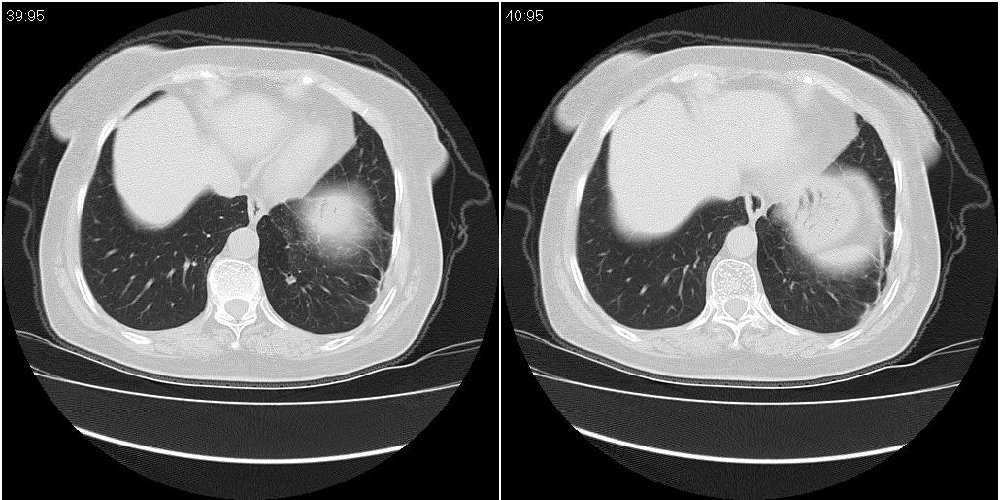

女性,72岁。去年9月份发现肺部病变,诊为肺结核并进行正规治疗至今,但复查后发现ct表现几乎没有变化。

右侧中叶支气管明显狭窄,建议行纤支镜检查!

右中间段支气管局限性狭窄,右中叶支气管亦稍显狭窄,但并未见明显占位表现,半年多了,无变化也许是好事,可能为炎性狭窄,建议继续随访。

双肺继发型tb并右中叶内膜tb,轻度支扩,左下胸膜肥厚粘连。

右中叶炎性改变,支气管狭窄但较光滑,占位可能性不大。

右中间段支气管局限性狭窄,右中叶支气管亦稍显狭窄.

双肺继发性肺结核并右肺中叶节段性肺不张,左下胸膜肥厚粘连。

右肺中叶节段性肺不张,考虑结核或慢性炎症,建议做纤支镜检查。

双肺继发性肺结核并右肺中叶节段性肺不张